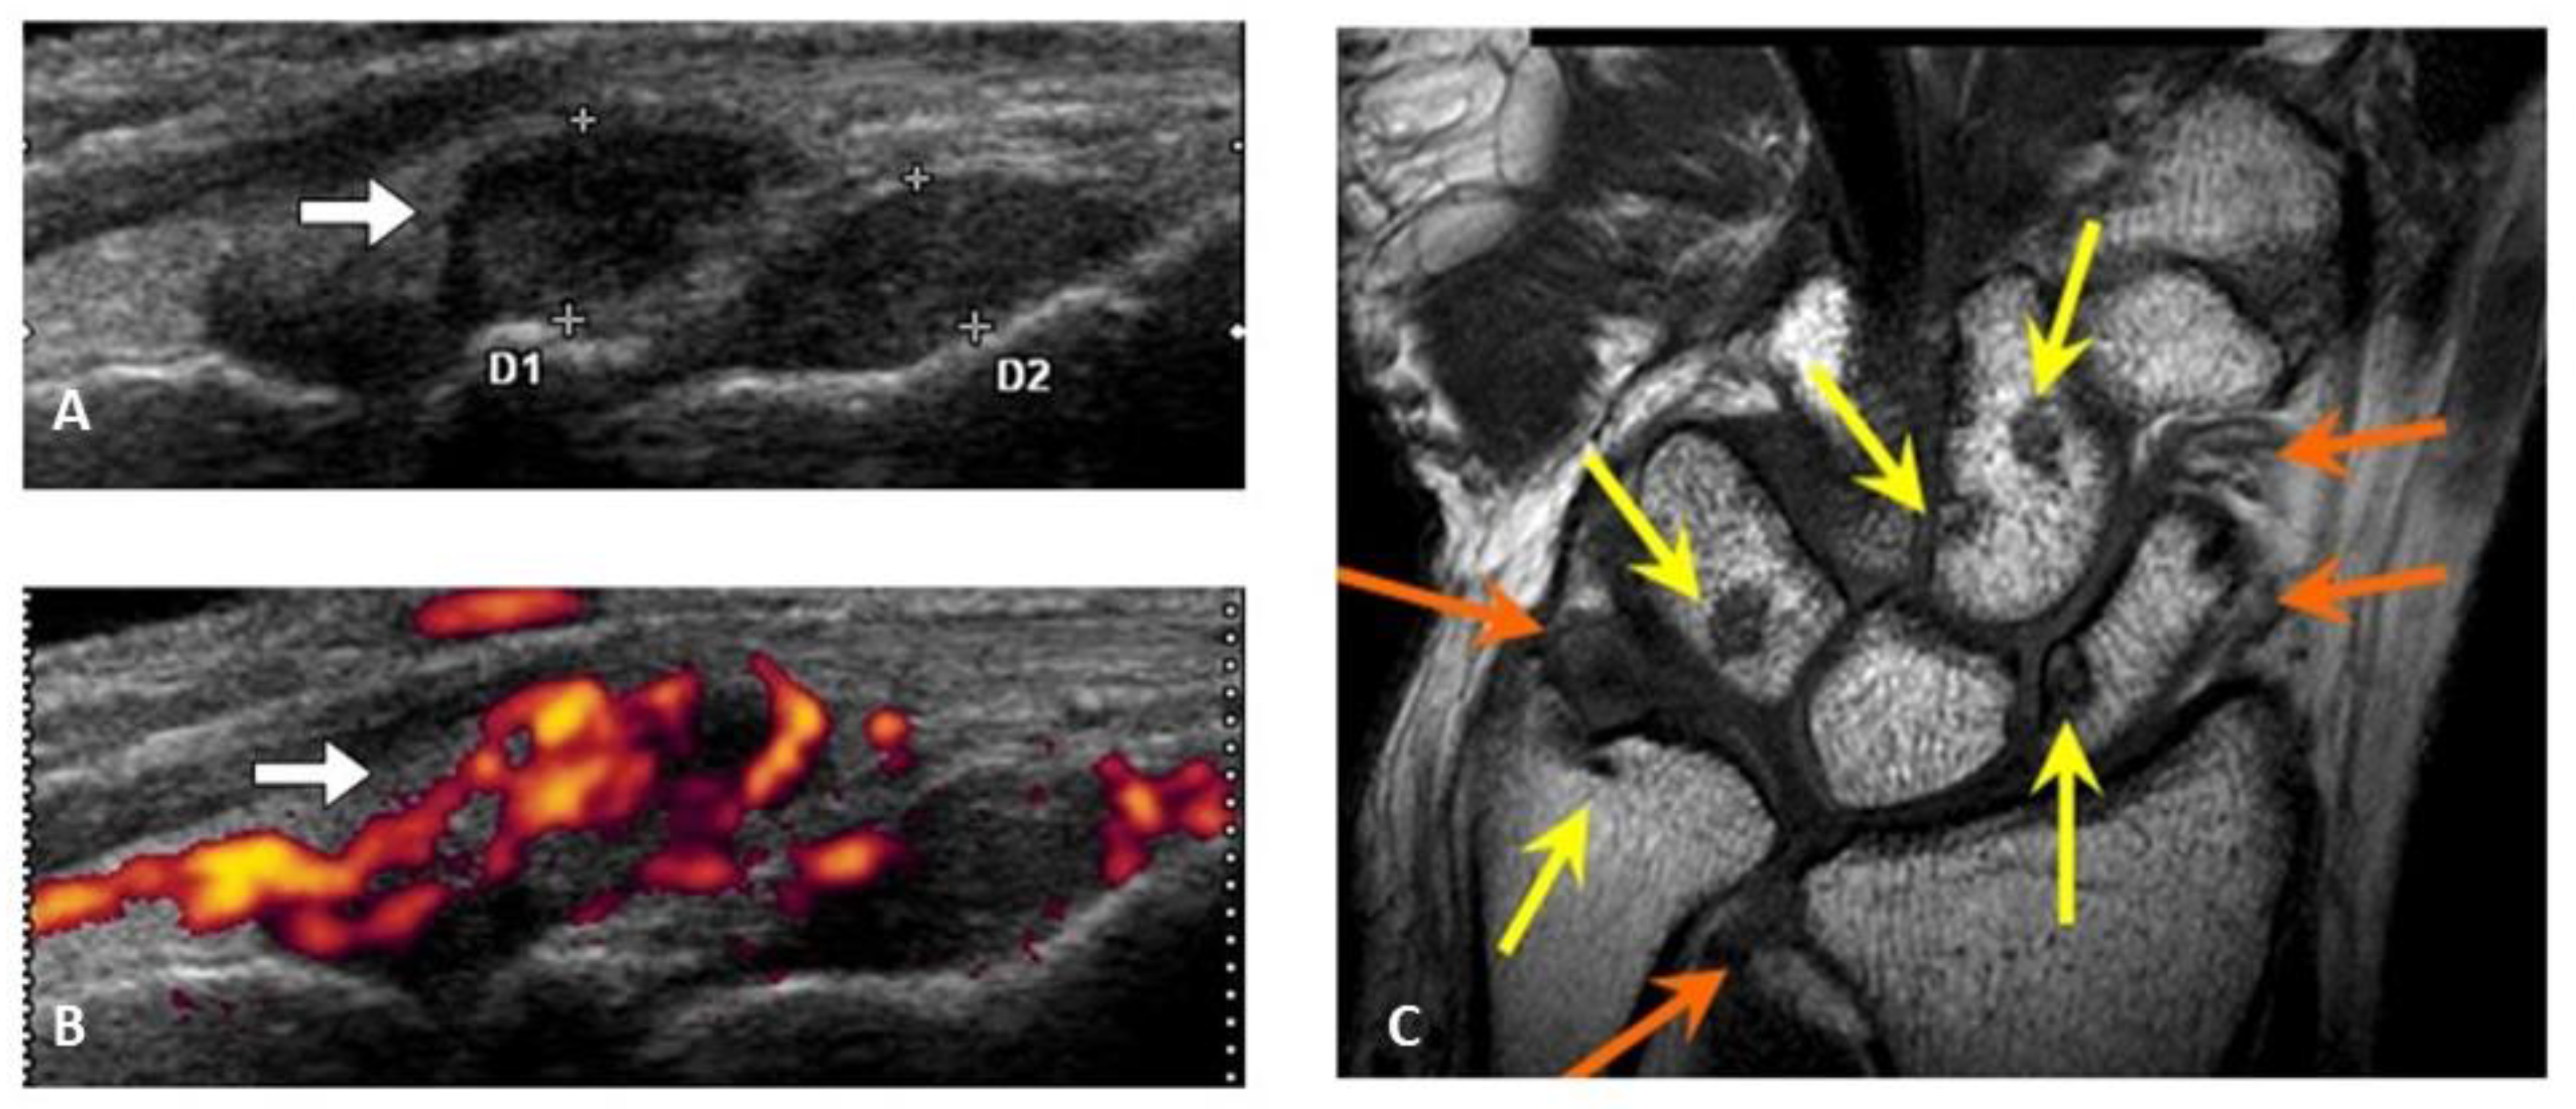

Figure 2. Rheumatoid synovium by ultrasonography and bone erosion by MR-imaging. Synovial hypertrophy (white bar) by systematic multiplanar grayscale ultrasonography (A), marked signals of synovial flow by power doppler ultrasonography (B), bone erosion ((C), yellow bar) and synovial hypertrophy ((C), orange bar) by MR-imaging are characteristic images in rheumatoid arthritis.